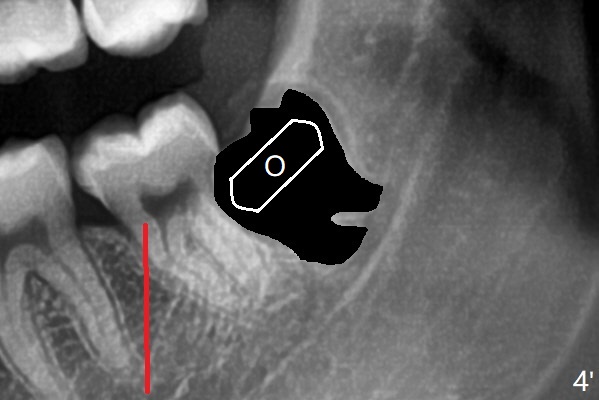

A 22-year-old man will return for 3rd molar extraction (4 of them, Fig.1-4). Prepare 2 or 3 #15 blades and 1-2 extra surgical burs. Since the third molars may overlap with the second ones, oblique incision (red line in Fig.4') will be mesial. Place Collagen and Osteogen plugs in the #32 and 17 sockets, respectively (Fig.4': C, O). As the roots are short and bone formation distal to the 2nd molars is critical, the plugs will be placed horizontally and coronally (Fig.4' white outline). No dovetail is needed. Pan 4 BW will be taken immediately and 3-4 months postop. The experiment will confirm whether collagen plug is enough to facilitate socket bone healing. In fact extraction of #1 turns out to be extremely difficult. There is not enough time for #16 and 17 extraction in one appointment (Fig.5).